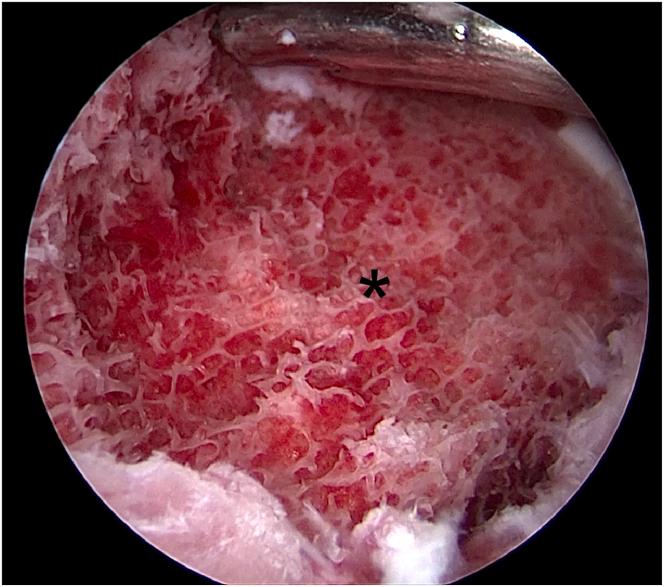

Few cases of anterior cruciate ligament (ACL) tibial avulsion injuries occur in adolescents. Bony ACL avulsion from the tibial side has been treated by various methods ranging from conservative management to a wide range of operative procedures. Various arthroscopic operative procedures are available to reduce and fix these fractures. We describe a technique of arthroscopic "8" knotted fixation without any tibial tunnels for tibial-sided ACL avulsion. This simple technique avoids the potential complications of hardware fixation within a joint. It represents an arthroscopic treatment option for ACL tibial avulsion injuries.

青少年前交叉韧带(ACL)胫骨撕脱伤的病例很少见。从保守治疗到广泛的手术操作,胫骨侧ACL骨撕脱伤有多种治疗方法。有多种关节镜手术可用于复位和固定这些骨折。我们描述了一种关节镜下“8”字打结固定技术,用于胫骨侧ACL撕脱伤,无需任何胫骨隧道。这种简单的技术避免了关节内硬件固定的潜在并发症。它代表了一种治疗ACL胫骨撕脱伤的关节镜治疗选择。